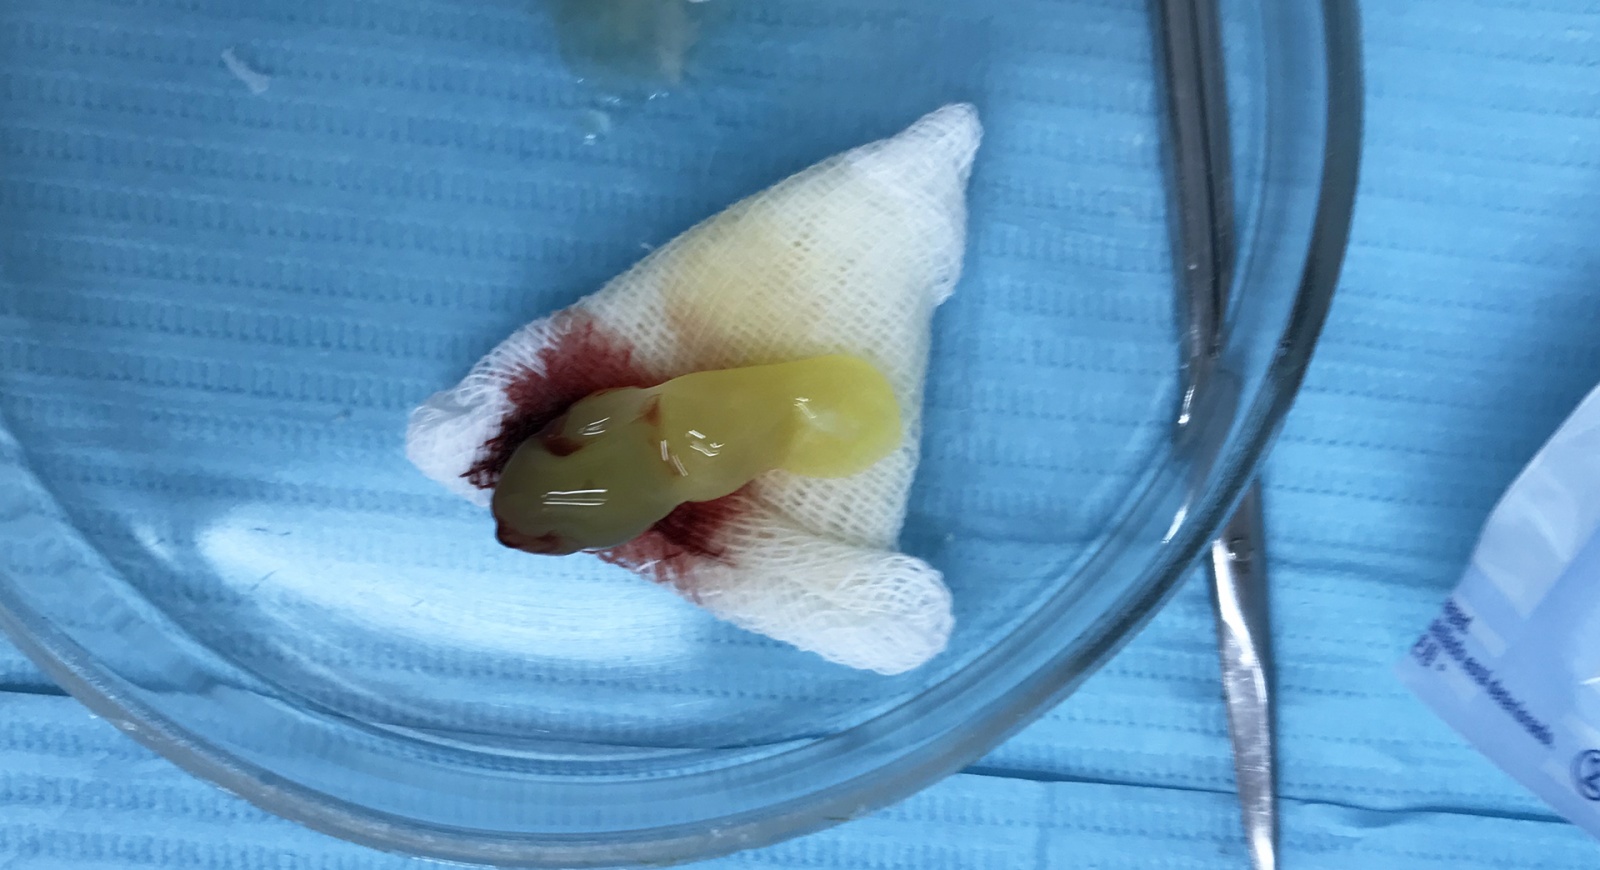

Вот сам зуб. Внешне все хорошо, а вот внутри, нет.

Зуб растачивается, специальным образом, чтобы удаление было с минимальным травмированием. Растачивают зуб в зависимости от того, сколько у него корней.

После расточки вынимают по частям. Растачивал зуб мой стоматолог (терапевт-ортопед), а уже остальные операции проводил его коллега, хирург-имплантолог.

4.4. После взятия крови, приступили к удалению зуба.

Процедура прошла совершенно безболезненно: я и представить себе не мог, что зуб удаляется так легко и совершенно безболезненно.

После удаления, я захотел сфотографировать части удаленного зуба, но ассистентка хирурга сказала, что зуб уже в урне. Так что сорри, фотографий частей зуба не будет.